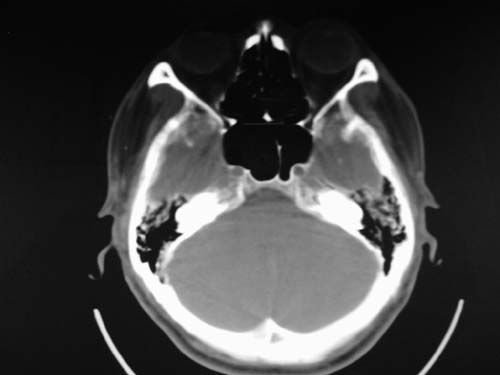

标题: CT17020:是硬膜下的吗?

脑中线内血肿,是硬膜下的吗?

硬膜下血肿,有颅骨骨折

支持镰旁硬膜下血肿,颅骨骨折,头皮损伤.

这个病人年龄不小吧,右侧脑沟不清,中线结构稍有左移,右侧额颞顶及右镰旁硬膜下血肿,另有蛛血,骨折。

外伤后引起的颅骨骨折、硬膜下血肿、皮下血肿,颅骨骨折引起的矢状窦破裂,形成大脑纵裂内血肿。